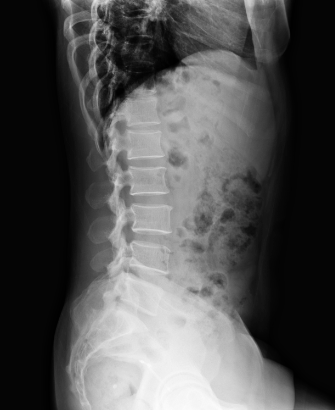

In this study, we aim to initiate the development of Radiology Foundation Model, termed as RadFM.We consider the construction of foundational models from the perspectives of data, model design, and evaluation thoroughly. Our contribution can be concluded as follows: (i), we construct a large-scale Medical Multi-modal Dataset, MedMD, consisting of 16M 2D and 3D medical scans. To the best of our knowledge, this is the first multi-modal dataset containing 3D medical scans. (ii), We propose an architecture that enables visually conditioned generative pre-training, allowing for the integration of text input interleaved with 2D or 3D medical scans to generate response for diverse radiologic tasks. The model was initially pre-trained on MedMD and subsequently domain-specific fine-tuned on RadMD, a radiologic cleaned version of MedMD, containing 3M radiologic visual-language pairs. (iii), we propose a new evaluation benchmark that comprises five tasks, aiming to comprehensively assess the capability of foundation models in handling practical clinical problems. Our experimental results confirm that RadFM significantly outperforms existing multi-modal foundation models. The codes, data, and model checkpoint will all be made publicly available to promote further research and development in the field.